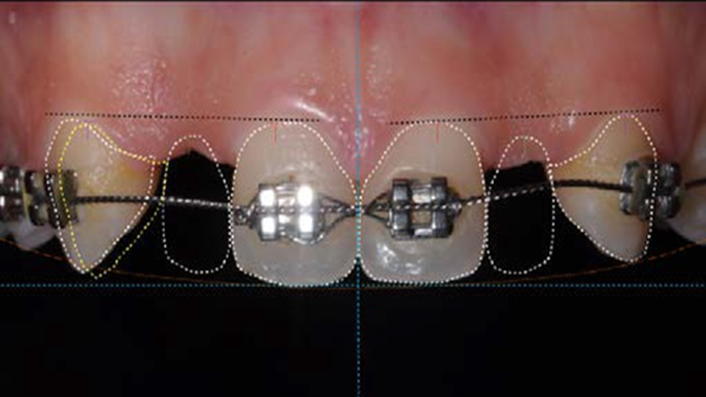

Socket Shield Technique, anterior esthetics, maxillary anterior, esthetic, esthetics, delayed implant placement, socket preservation, AnyRidge, Root Membrane Kit, Root Membrane Technique, Partial Extraction Therapy, PET, esthetic zone, fuse abutment, Dr. Yoshiharu Hayashi,#11,#21,#22

Anterior esthetics, MiNi, flap elevation, minimally invasive technique, soft tissue management, esthetic zone, Dr. Achraf Souayah, anterior aesthetics, aesthetic, aesthetics, esthetic, #12, #22